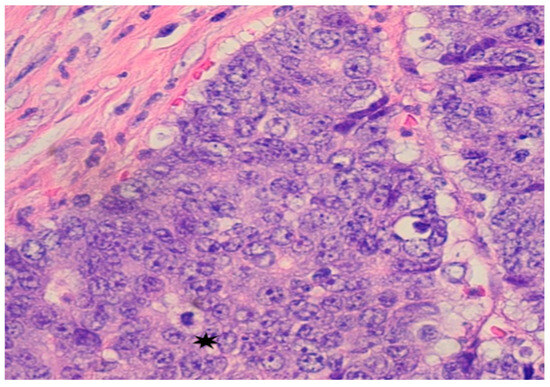

Subsequent colonoscopy identified a large cecal mass. Histopathological analysis of biopsy samples revealed a moderately to poorly differentiated adenocarcinoma. Microscopy demonstrated malignant cells with irregular, hyperchromatic nuclei, prominent nucleoli, and frequent mitotic figures (Figure 2). Immunohistochemistry confirmed intact nuclear expression of all mismatch repair (MMR) proteins, indicating microsatellite-stable (MSS) status. Immunohistochemical staining for mismatch repair (MMR) proteins showed intact nuclear staining, indicating microsatellite-stable (MSS) status. PD-L1 immunohistochemistry (22C3 pharmDx assay) was also performed on the primary tumor and revealed a tumor proportion score (TPS) of <1%, with minimal immune-cell staining. Despite low PD-L1 expression, the decision to proceed with immunotherapy was supported by the presence of an ultra-mutated POLE mutation and a high TMB, both recognized as predictive biomarkers for immune checkpoint inhibitor response.

Figure 2. Pathology from Colonoscopy: Mass in cecum identified as poorly differentiated adenocarcinoma; malignant cells show large and irregular nuclei with prominent nuceoli and mitotic figures *.